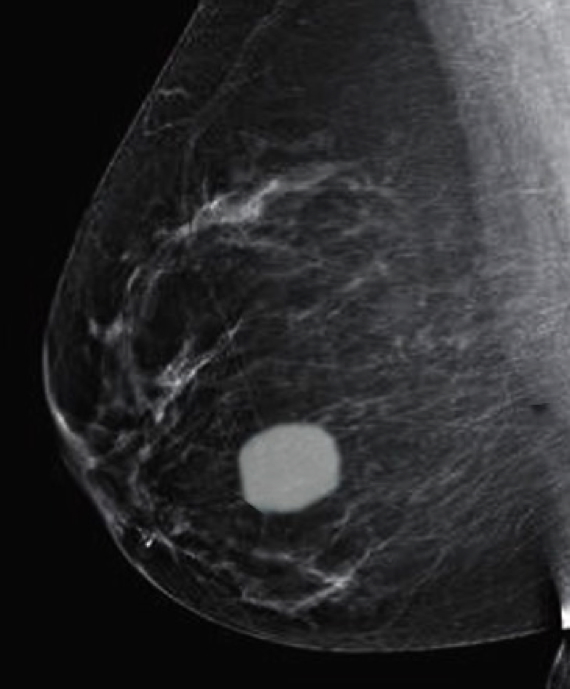

- Most common benign tumour of the breast

- Usually affects women aged 20–40 years

- Mammographic density or calcifications

- Size: usually <5cm

- ~50% undergo spontaneous involution

- No risk of malignancy

- Surgical excision is curative but often unnecessary

2. Fibroadenoma of the Breast, Lori A. Erickson, MD; Beiyun Chen, MD, PhD, DOI: https://doi.org/10.1016/j.mayocp.2020.08.040